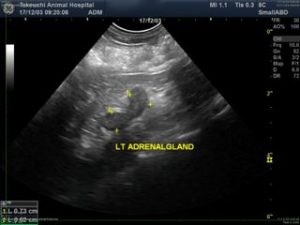

★超音波検査(腹部エコー)

副腎の形態は保ったまま大きくなっている所見がみつかります。正常な形はピーナッツ型やコンマ型と表現される特徴的な形をしています。

同時に超音波検査をした画像がこちらです。

厚いところでは7mmを越えています。この子はチワワですので計測上は「大きなサイズの副腎」ということになります。

小型犬で、6mmを越えている場合には副腎過形成を強く疑う所見です。